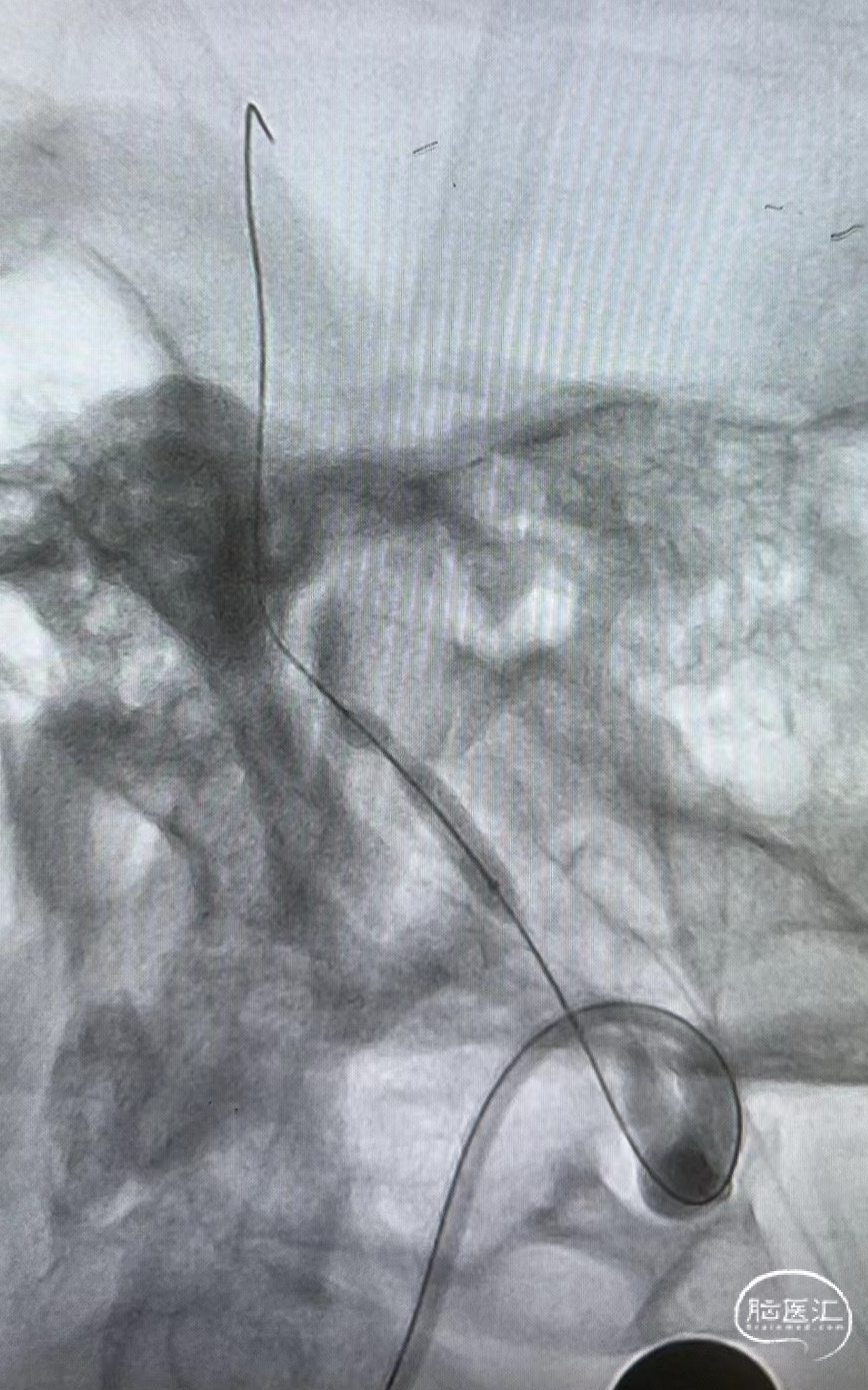

远端通路导管到位。

微导丝通过病变。

赛诺Neuro LPS®颅内球囊扩张导管 2.75*15mm输送至病变位置。

缓慢扩张至命名压3atm。